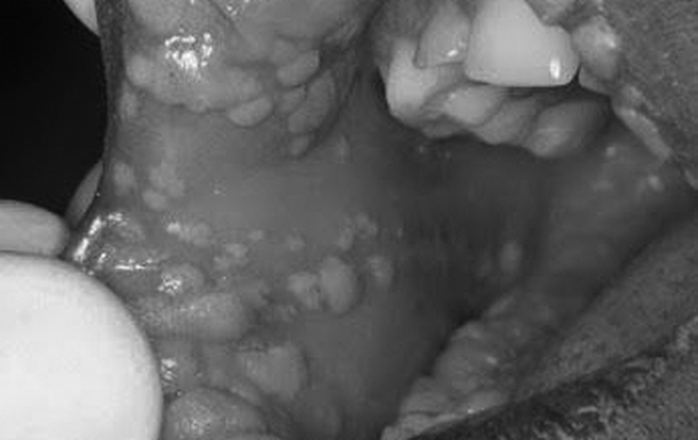

HPV - It is not the Hanky Panky Virus the media says it is: Oral Abnormality Screening and the Health Care Provider

New evidence has linked the presence of HPV in an oral mucosal infection to the increase risk of oral and oral pharyngeal cancer. It has been a challenge in the …